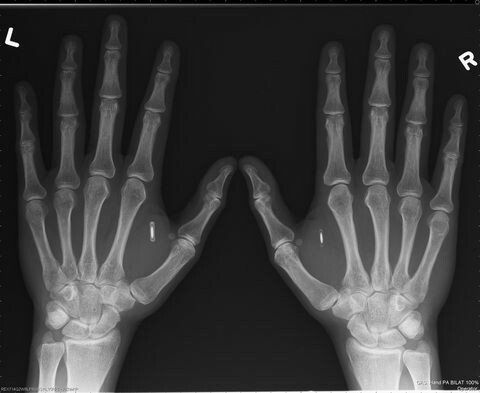

치과에서 임플란트 시술후

마인드컨트롤전파무기피해가

시작되서 임플란트를 뽑아 속을 보니 RFID칩이 발견되어 법정승소하는데 ~결정적인 증거로 작용되었다!

자신의 신체에 임플란트가 느껴지는

마인드컨트롤전파무기피해자는

TI (TargetedIndividuals)로 불립니다.